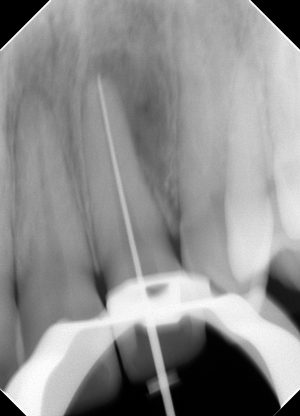

作業長を決定し、

根管充填。

ここまで、1日で行います。